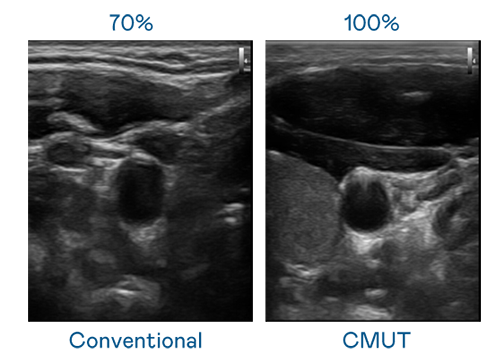

CMUT 技术是一种用电容式微机电元件来产生超音波讯号的技术。与传统 PZT 压电式技术相比,CMUT 频宽增加 30%,更宽频的超音波讯号让影像解析度大幅提升,是实现高影像品质医疗超音波扫描、促进精准医疗发展的关键技术。

大频宽带来超清晰影像

超音波影像的解析度高低,首先取决于探头能发出的讯号频宽。凯发k8 CMUT 可提供高清晰的超音波讯号,提供高频宽、高灵敏度、影像纹理细节更高的超音波影像,协助医护人员缩短影像判读时间及利用精准的医疗影像进行诊断。